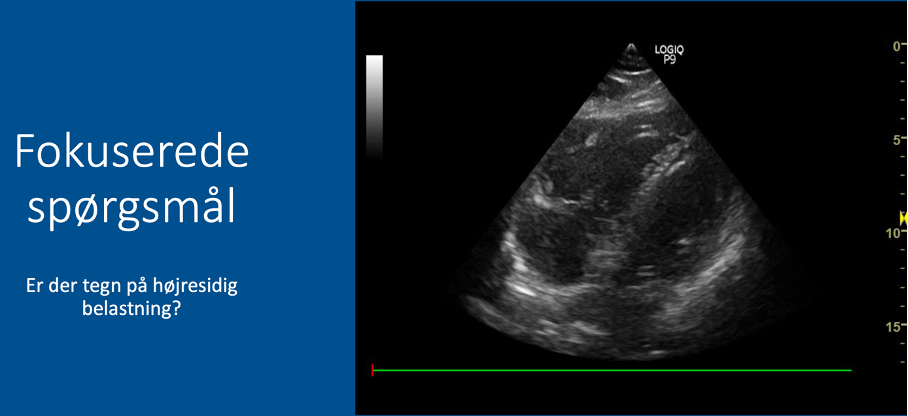

Fokuserede spørgsmål (FHUS):

* Tegn på højresidig belastning: ja/nej?

Vurder størrelsesforhold mellem højre og venstre ventrikel:

* Normalt forhold: VV (2/3) er omtrent dobbelt så stor som HV (1/3) –> INGEN tegn på højresidig belastning

* Abnormt forhold: hvis HV ≈ VV eller HV > VV –> tegn på højresidig belastning

A